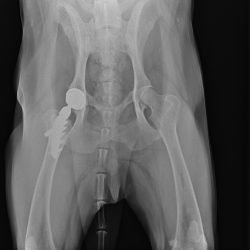

骨折や脱臼、前十字靭帯断裂、関節疾患など、犬や猫の「動くこと」に関わるさまざまなトラブルに対応しています。

CTなどの画像診断を活用し、原因を正確に見極めたうえで、外科手術からリハビリまで一貫した治療を行います。